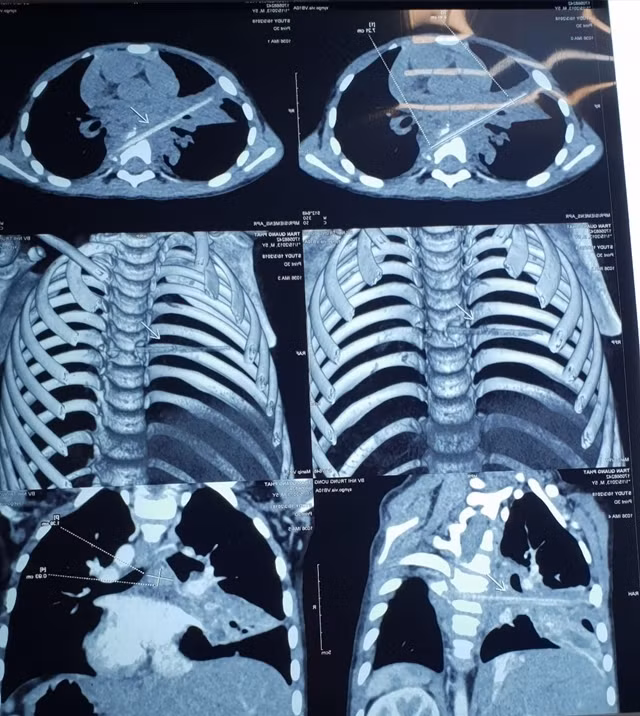

Đầu tháng 10 vừa qua, cháu Nguyễn V.M (5 tuổi, Thái Bình) được gia đình chuyển lên Bệnh viện Nhi TƯ do viêm phổi tái diễn nhiều lần. Khi chỉ định cho bệnh nhi chụp cắt lớp vi tính 128 dãy, các bác sĩ của bệnh viện nhận thấy, trên phim chụp có hình ảnh điểm vôi hóa cột sống và hình ảnh viêm phổi thùy bên phải nhưng không rõ có dị vật vì dị vật không cản quang.

Hình ảnh que nứa dài 9cm trong cơ thể M. trên phim chụp

Hình ảnh chụp vi tính cắt lớp sau đó cho thấy, bệnh nhi có một dị vật dài nhọn kích thước 72x4mm tại vị trí nhu mô thùy phổi ở thùy giữa phổi phải. Dị vật này đi từ trước ra sau, xuyên qua khe giữa 2 thân đốt sống 6, 7 và làm vỡ thân đốt sống. Khi nằm lại trong cơ thể, dị vật gây phản ứng thâm nhiễm viêm trung thất sau quanh đốt sống 6, 7. Đây cũng chính là nguyên nhân khiến cháu M phải vào viện vì viêm phổi trong suốt 8 tháng.